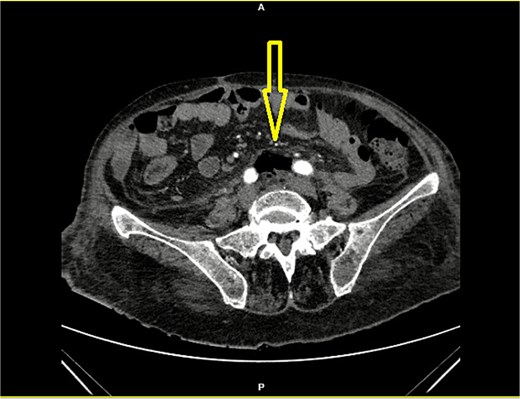

An 84-year-old female patient presented with massive hematochezia without a physiologic bowel movement that day. Previous comorbidities reported were hypertension and diabetes mellitus. Two months ago, the patient reported being treated with blood units due to unexplained anemia, with no further diagnostics conducted. On admission, the abdominal physical exam was unremarkable. The digital rectal exam revealed blood in the rectum. The laboratory test revealed a low erythrocyte count of 2.36 × 106/μL (3.93–6.08), Hemoglobin level of 7.8 g/dL (11/2–17.5), Hematocrit % of 24.3 (34.1–51), Leucocyte count of 18.1 × 103/μL, Neutrophil % of 85.7 (34–71.1), serum glucose level of 24.5 mmol/L (3.3–5.6), and albumin level of 33 g/L (34–50). The patient was admitted for resuscitation and further investigation. Two units of blood were given. A diagnostic colonoscopy performed the next day revealed sigmoid diverticulosis and a solitary mid-rectal diverticulum with a wide opening and necrotic bottom (Fig. 1). The patient presented with two episodes of fever, reaching a maximum of 38.3°C. On the third day of admission, an elevated level of procalcitonin (27 ng/mL), (0.05–0.1), Leukocytosis of 23.0 × 103/μL, and a CRP level of 248 mg/L (0–5) were noted. The general condition of the patient slightly worsened, and the repeated abdominal physical exam remained unremarkable. A contrast-enhanced abdominal computerized tomography showed free air around the mid rectum in the pelvis (Fig. 2) with cranial retroperitoneal extension (Fig. 3). Emergency laparotomy was indicated. No signs of peritonitis were noted. After rectal mobilization and dissecting distally, a gas bubble occurred. Further distal dissection revealed a small abscess on the anterolateral wall with a visible opening in the rectal wall. A low Hartmann procedure was performed (Fig. 4). The postoperative period was uneventful. The length of hospital stay was 9 days. Pathology analysis confirmed the presence of a solitary rectal diverticulum perforation with accompanying diverticulitis.

Contrast-enhanced CT of the abdomen showing retroperitoneal air (arrow) below the aortic bifurcation (between the common iliac arteries).